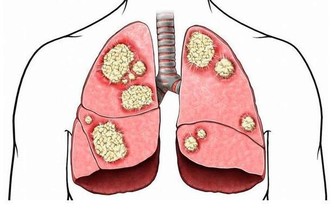

對絕食並且死亡的人進行檢查後,揭示了以下可能的死亡原因:

多器官衰竭;

心室顫動或快速心律,導致心臟泵血作用不佳,並可能導致意識喪失甚至死亡;

嚴重膿毒症(血液中毒),身體因感染而傷害自己的器官和組織。